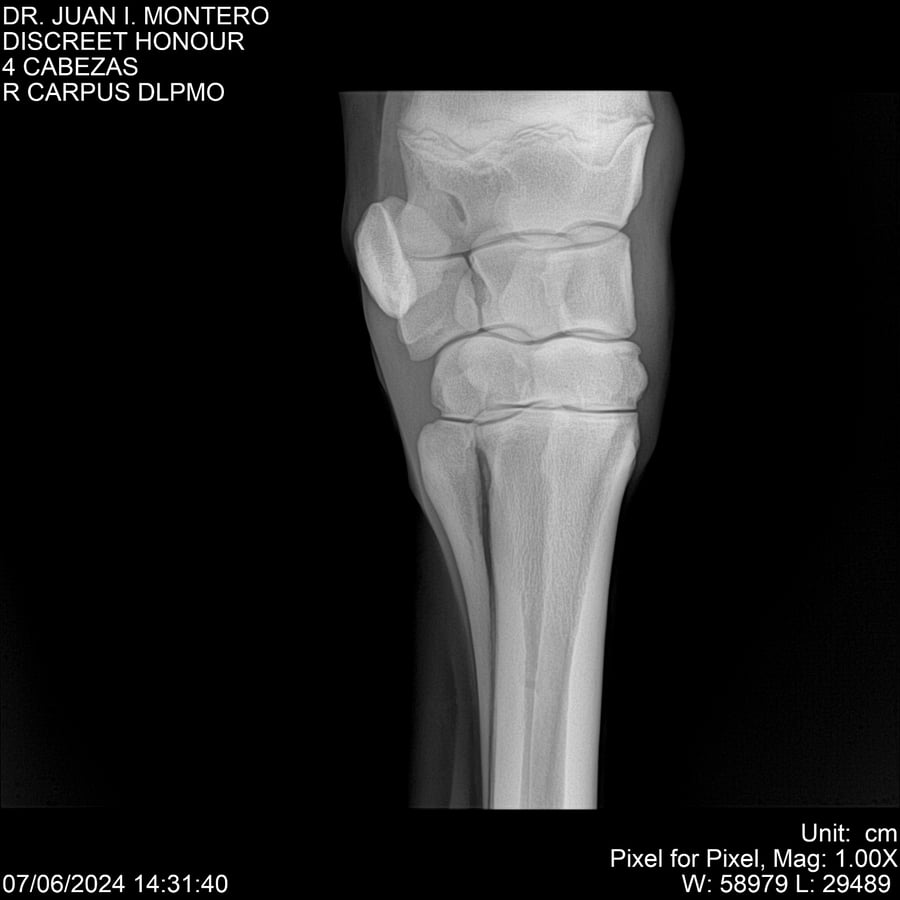

LOTE 6, DISCREET HONOUR 🔥 🔥 🔥 Lote Anterior Volver al remate Lote Siguiente Ficha Contacto Montevideo - Ficha del Lote Identificador: #281093 Categoría: Yeguarizos Montevideo - 82 Visualizaciones ClicData Contacto Empresa: Abelenda N. R., Walter Hugo Nombre*: Teléfono* : E-mail* : Mensaje Enviar Registrese gratis Este contenido Exclusivo está disponible sólo para usuarios registrados Ingresar